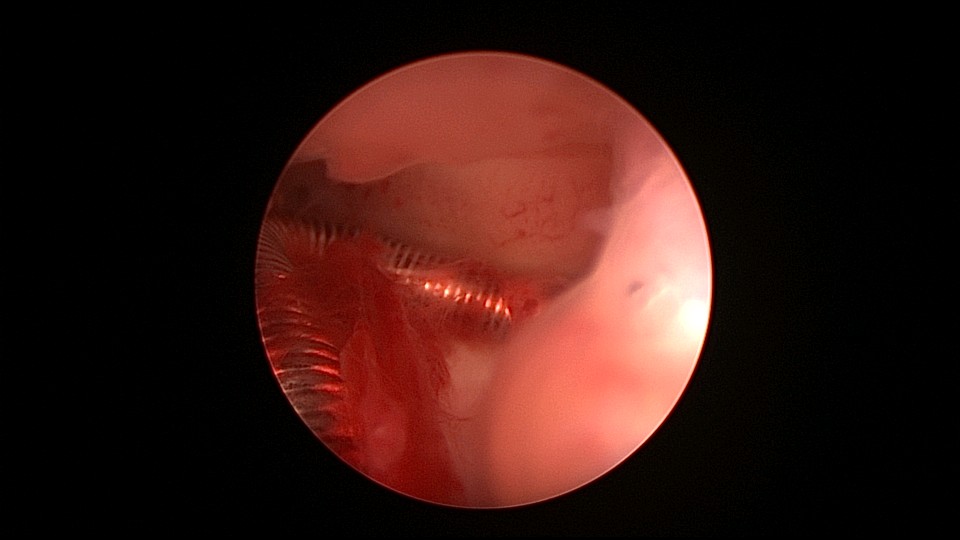

患者38岁,G2P1,剖宫产1次。安环13年,发现内膜息肉3年伴月经淋漓不净。2025年3月行宫腔镜取环、息肉切除,同时放置曼月乐环并固定。子宫后位,宫深7.5cm,宫型环位置正常,宫颈管及宫腔后壁见息肉,顺利取出节育环,切除息肉送病检,4-0不可吸收线将曼月乐缝合固定于宫腔上段后壁,第一次做宫腔镜下缝合固定节育环,体外打结后推结到位比较困难,今后改进缝合固定方式。病检为子宫内膜息肉及增殖期子宫内膜。2025年4月复查B超,曼月乐位置正常,环顶端距宫底1.3cm。